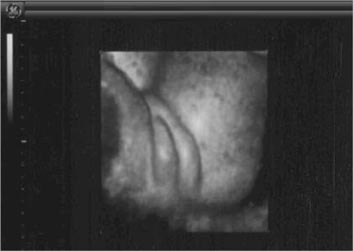

Im Verlauf der 5. SSW gelingt die Darstellung der Fruchthöhle mittels Vaginalultraschall bei normaler Anlage in der Gebärmutter. Die frühe Feststellung einer Fruchthöhle innerhalb der Gebärmutter schließt eine Eileiterschwangerschaft zu 99% aus. Am 34. Schwangerschaftstag (nach Regelblutung) ist diese 3mm groß. Die Darstellung der Herzaktion ist ab dem 48. Tag möglich. Ab einem mittleren Fruchthöhlendurchmesser von 20mm sollte die Herzaktion ebenfalls nachgewiesen werden können.